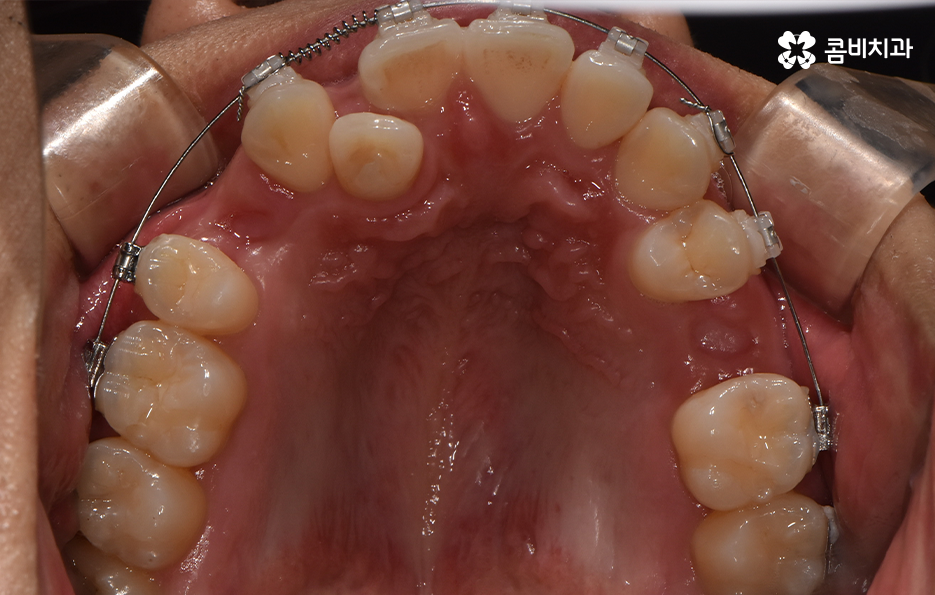

덧니가 나는 원인은 유전적인 영향부터 골격적인 부분 등 다양하지만 기본적으로는 치아가 나올 공간이 부족해서 덧니의 형태로 영구치가 자라는 경우가 많기 때문에 덧니 교정 사례에는 유독 발치 교정 사례가 많이 있는데요

다만 덧니 교정 사례에서 발치교정 사례가 많은 이유는 턱뼈가 좁아서 치아가 덧니로 자란 경우가 많기 때문에 치열을 재배열하기 위해서는 치아가 움직일 수 있는 충분한 이동공간이 필요하기 때문에 공간 확보의 목적으로서 작은 어금니 양옆, 위아래 4개를 발치를 하는 발치교정법이 보편적으로 많이 활용되고 있으며 치아의 이동 공간을 확보하는 방법으로는 발치 교정법 외에도 악궁확장, 어금니 후방이동, 치간삭제와 같은 비발치적인 방법도 가능하기 때문에 치아를 얼마나 이동시켜야 할지에 따라서 치료법은 개인차가 발생되고 있어요

발치교정이 필요한지 여부에 대한 판단은 치아의 이동 공간이 얼마나 필요하고 확보해야 하는지에 따라 달라지는데 이러한 판단 근거는 단지 치열만을 두고 보는 것이 아니라 골격과 얼굴형을 종합적으로 고려한다는 점에서 정밀검진과 함께 풍부한 경험을 갖춘 교정 전문의와 잘 상의하여 결정하신다고 보시면 될 거예요